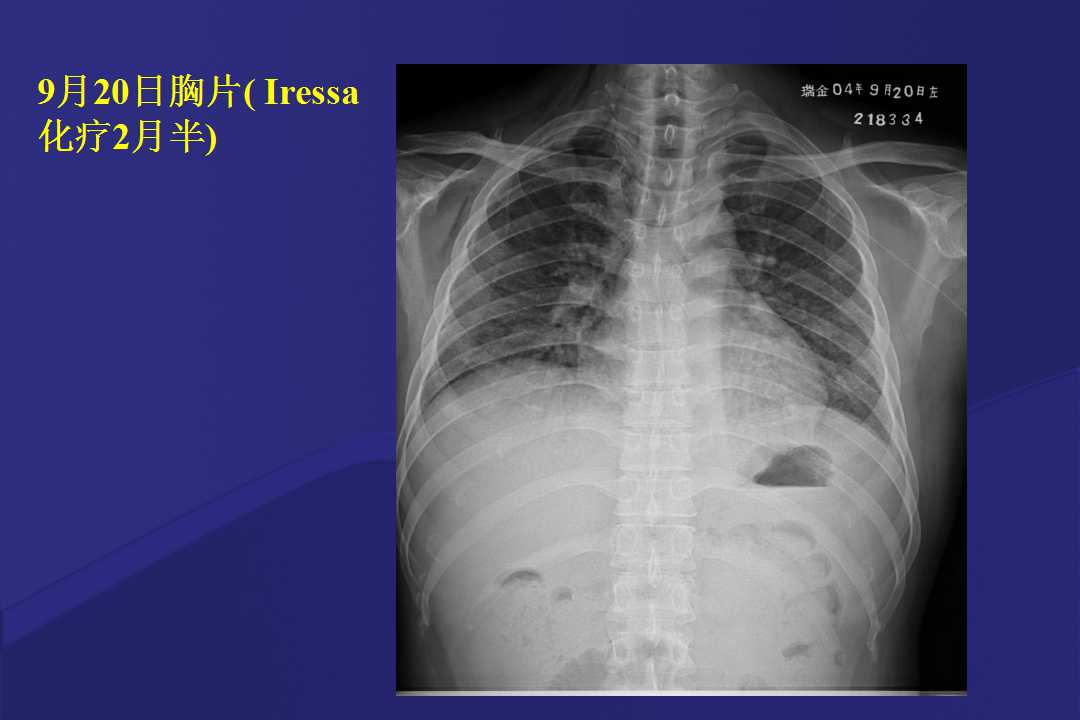

血液疾病患者肺部并发症影像学表现